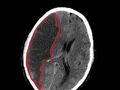

Лучше два инфаркта, чем один инсульт?

Лучше два инфаркта, чем один инсульт? Собственно, так говорят не врачи, а пациенты. Действительно, после инсульта, которые у нас в России носят крайне тяжелый характер, качество жизни всей семьи больного резко падает. У нас инсульт как причина смерти занимает второе место после инфаркта миокарда. И где же выход? Медики видят его в профилактике. Она вполне возможна и современна.